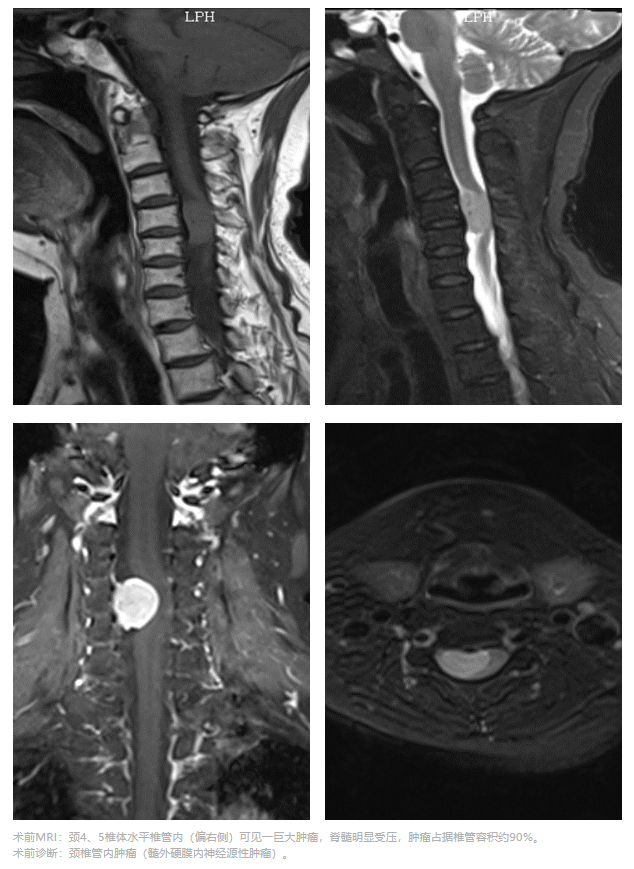

65岁的林阿姨,颈肩部疼痛伴右上肢疼痛、麻木5年,最近几个月愈发加重,辗转多家医院后林阿姨慕名来到附属翔安医院骨科,检查结果显示她的颈椎管90%已被肿瘤占据。

肿瘤像一枚“不定时炸弹”,压迫着林阿姨的脊髓,若肿瘤再进一步发展或不幸出现外伤,可能导致神经症状进一步加重,严重者将引起瘫痪,被命运扼住咽喉的林阿姨急需手术治疗。